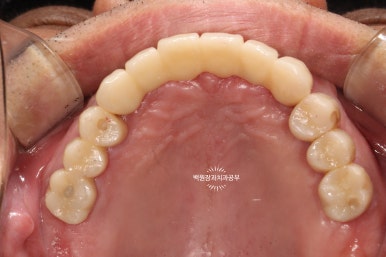

왼쪽이 위턱의 임시치아들이고, 오른쪽이 아래턱의 임시치아들입니다.

눈치 빠른 분은 아셨을거에요!! 위가 위턱, 아래가 아래턱입니다.

왜냐?! 지대주가 위가 8개, 아래가 6개잖아요~~ 제가 올려드렸던 치과용 파노라마를 확인해보세요!